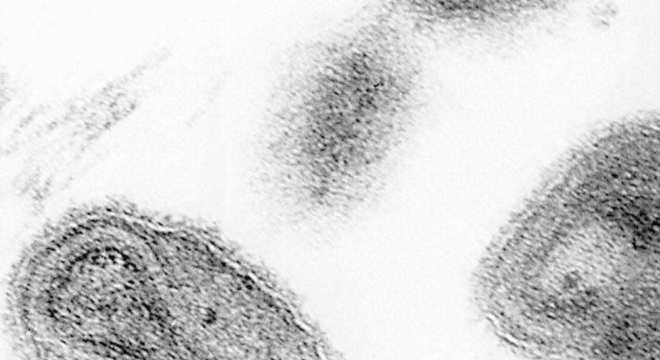

Em primeiro lugar, a varíola é uma doença infectocontagiosa provocada pelo vírus Orthopoxvirus variolae, da família Poxiviridae. No entanto, ela foi erradicada mundialmente por volta dos anos 1970 após uma campanha de imunização global sem precedentes organizada pela Organização Mundial da Saúde (OMS). Hoje, as amostras de vírus da varíola foram mantidas para fins de pesquisa.

– Microscopia eletrônica